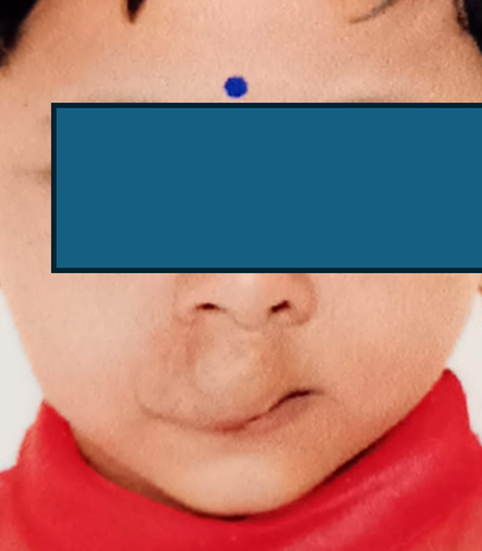

CONGENITAL ANOMALIES

CLEFT PALATE

CONGENITAL ANOMALIES

HEMANGIOMA